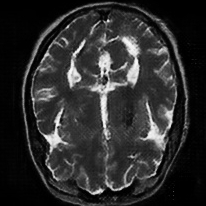

4.4 Qualitative Evaluation

In Figure 5 we analyze the prediction quality of our and compared approaches in a qualitative way. Considering modality propagation in MRI, we see that usage of uncertainty-aware patch invariance (UAPI) gives a better detailed weighting of the cerebrospinal fluid in the middle of the brain. In general, employing patch invariance yields better preservation of fine structures. This observation also applies to accelerated MRI enhancement. In particular, CUT and UAPI provide comparatively sharper knee images with more high-frequency details than the other methods.